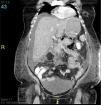

Se inició manejo con hidratación, analgesia y ayuno. Durante la primera semana, la paciente presentó dolor abdominal de difícil control con opiáceos, con síndrome de respuesta inflamatoria sistémica persistente, caracterizado por taquicardia y leucocitosis. Al quinto día, ante la falta de mejoría clínica se le realizó tomografía axial computarizada (TAC) simple de abdomen, donde se encontró páncreas sin presencia de necrosis, con colecciones líquidas peripancreáticas y en ambas goteras parietocólicas, además de engrosamiento a nivel de mesocolon. Continuó en ayuno hasta el séptimo día, cuando se decidió iniciar nutrición enteral por sonda nasogástrica, tolerándola adecuadamente. Durante la segunda semana presentó picos febriles, se realizaron hemocultivos resultando negativos; con mejoría del dolor y tolerancia de dieta enteral. Al día 14 de su estancia hospitalaria, presentó dolor en flanco derecho, además de distención abdominal importante, ausencia de peristalsis, vómito de contenido alimentario y datos francos de estado de choque. Por este motivo se trasladó a la unidad de cuidados intensivos, además de que se le realizó TAC de abdomen con contraste intravenoso (fig. 1), donde se documentó necrosis de grasa peripancreática y espacio pararrenal anterior izquierdo; el mesocolon mostró presencia de gas, además presentó cambios inflamatorios en colon transverso. Debido a la evolución tórpida y los datos encontrados en la TAC se realizó laparotomía exploradora en el día 14, donde se documentó líquido libre en cavidad abdominal, purulento, necrosis pancreática, así como del colon transverso (fig. 2), múltiples abscesos en mesocolon transverso; motivo por el cual se realizó colectomía total e ileostomía. Se trasladó a la paciente a la unidad de cuidados intermedios, al día 30. Al día 40 presentó fístula gastrocutánea, la cual se reparó quirúrgicamente. Presentó buena evolución clínica posterior, motivo por el cual el día 45 pasó a sala general hospitalaria y se dio de alta al día 60, completamente asintomática.